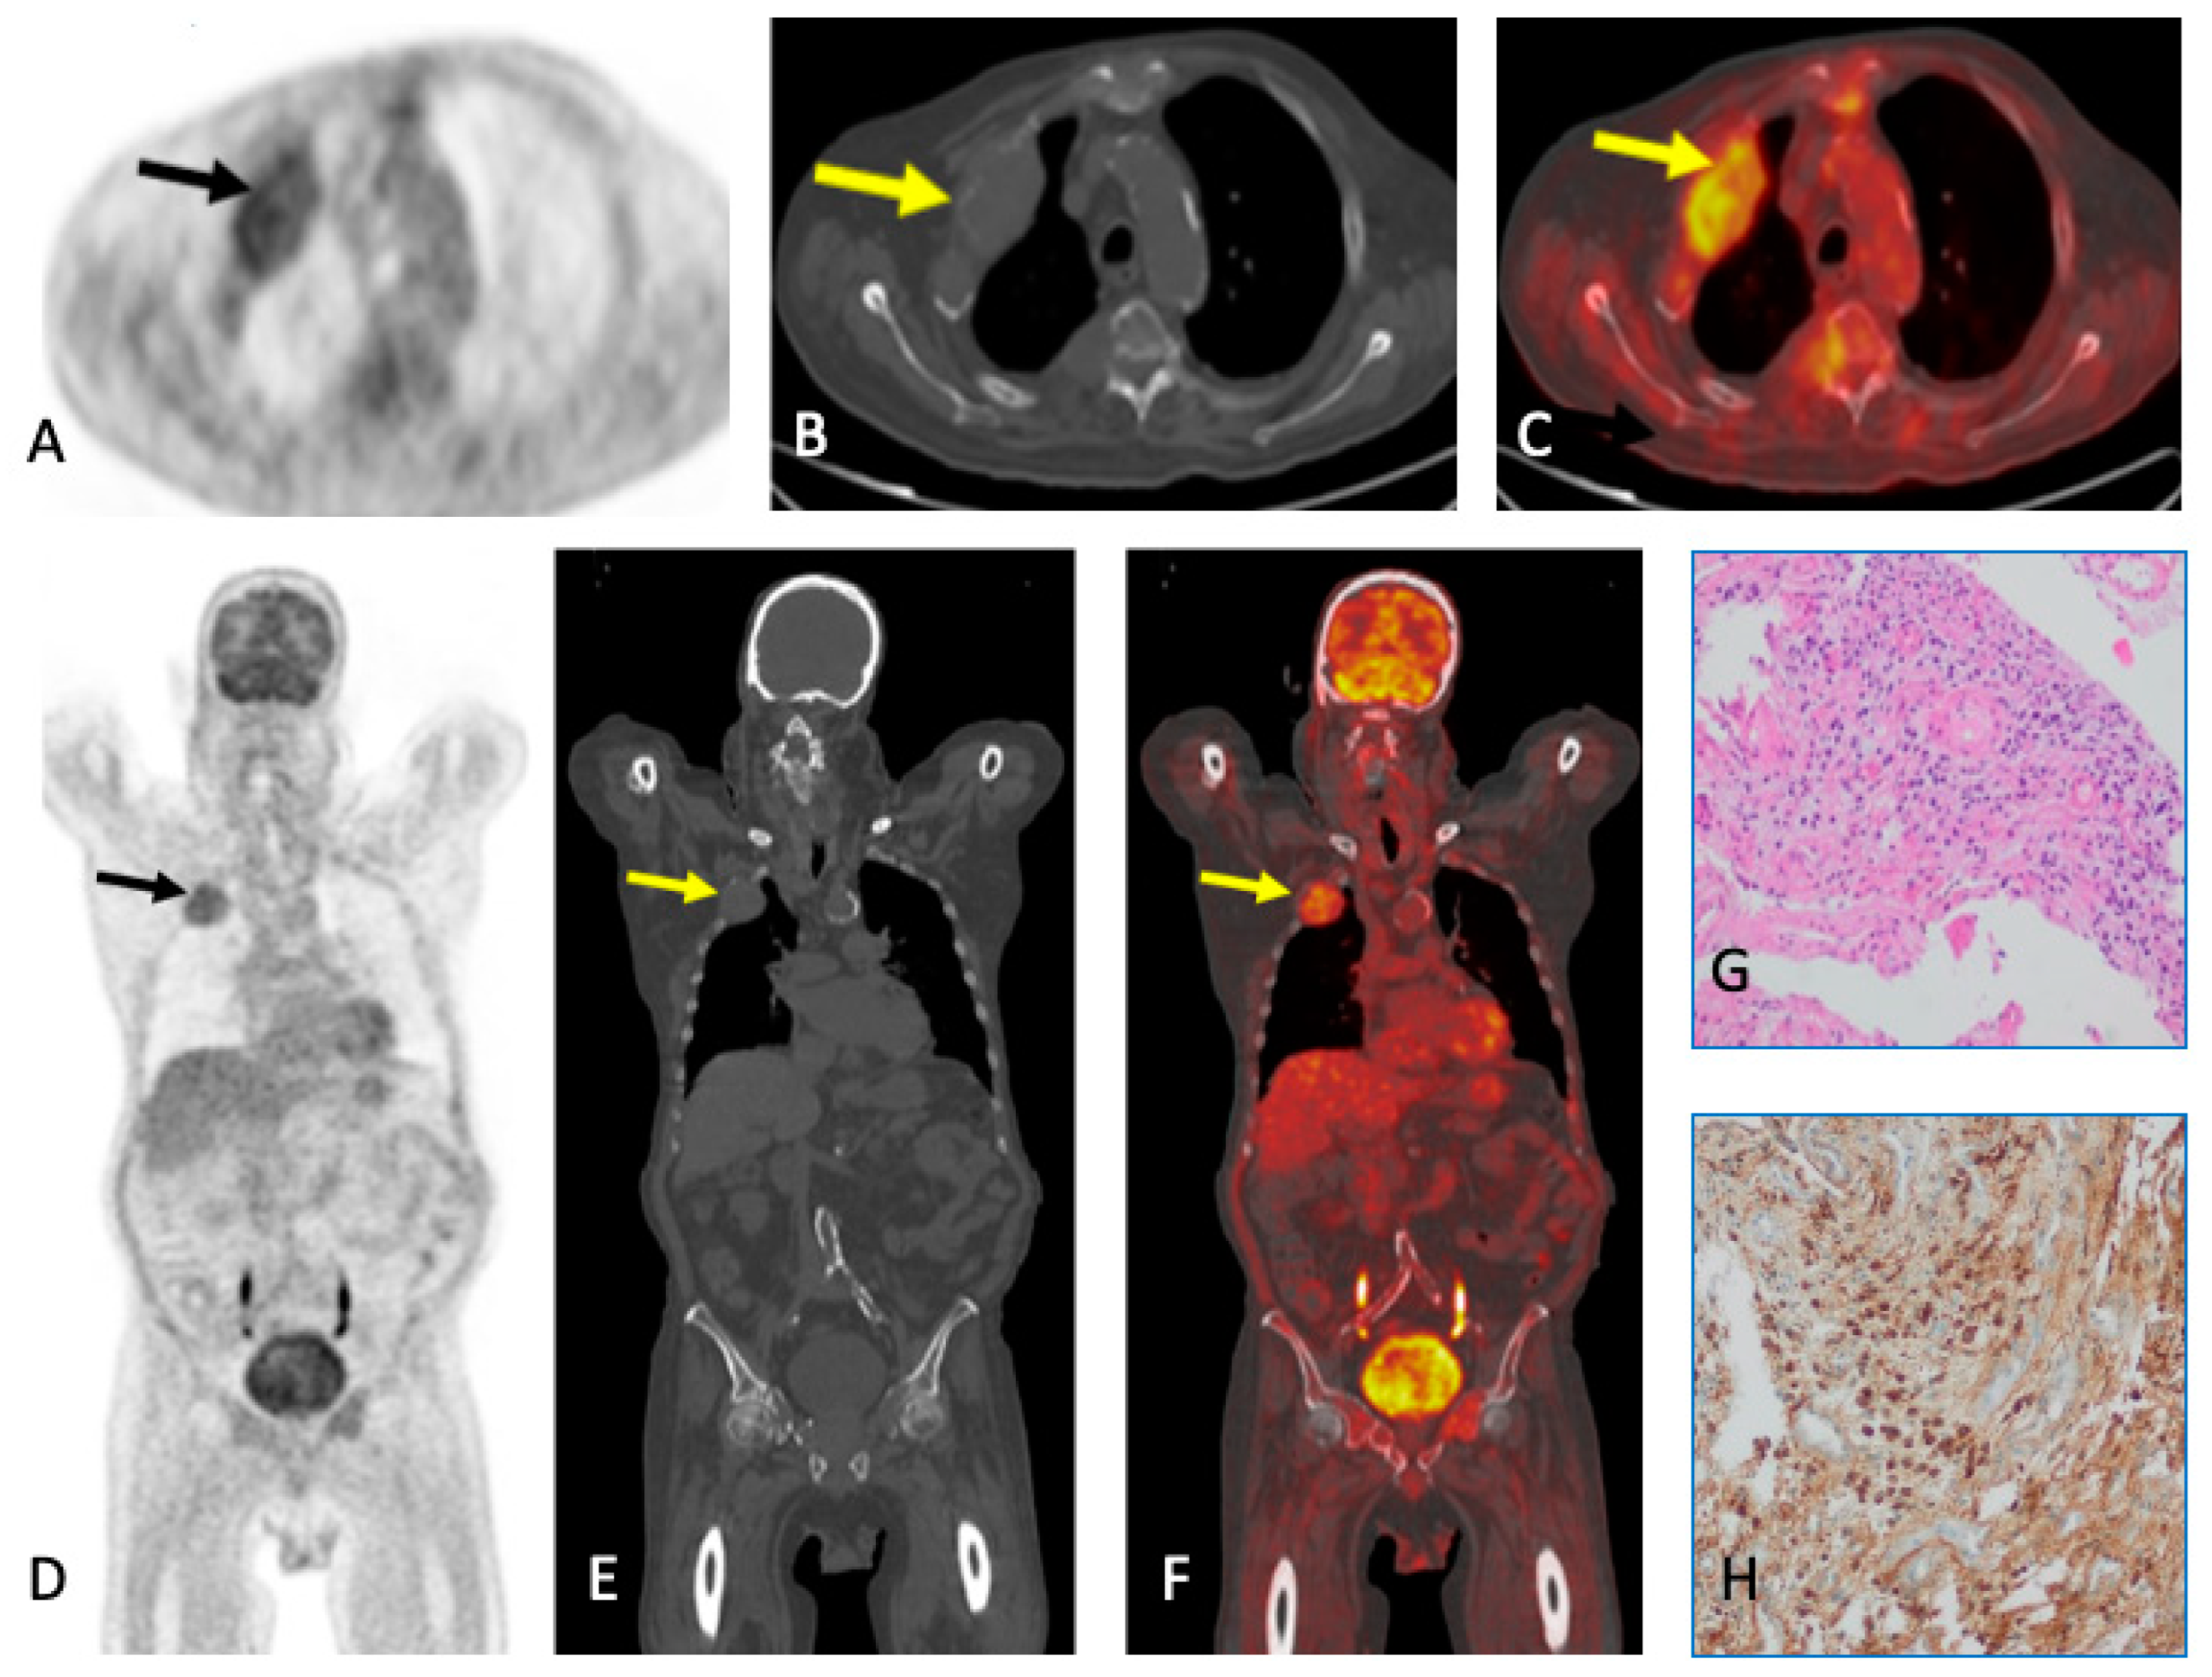

6. Plasmacytoma and Extramedullary MM

- Ooi, G.C.; Chim, J.C.-S.; Au, W.-Y.; Khong, P.-L. Radiologic Manifestations of Primary Solitary Extramedullary and Multiple Solitary Plasmacytomas. Am. J. Roentgenol. 2006, 186, 821–827. [Google Scholar] [CrossRef] [PubMed]

- Shen, X.; Liu, S.; Wu, C.; Wang, J.; Li, J.; Chen, L. Survival Trends and Prognostic Factors in Patients with Solitary Plasmacytoma of Bone: A Population-based Study. Cancer Med. 2021, 10, 462–470. [Google Scholar] [CrossRef]

- Caers, J.; Paiva, B.; Zamagni, E.; Leleu, X.; Bladé, J.; Kristinsson, S.Y.; Touzeau, C.; Abildgaard, N.; Terpos, E.; Heusschen, R.; et al. Diagnosis, Treatment, and Response Assessment in Solitary Plasmacytoma: Updated Recommendations from a European Expert Panel. J. Hematol. Oncol. 2018, 11, 10. [Google Scholar] [CrossRef]

- Salaun, P.-Y.; Gastinne, T.; Frampas, E.; Bodet-Milin, C.; Moreau, P.; Bodere-Kraeber, F. FDG-Positron-Emission Tomography for Staging and Therapeutic Assessment in Patients with Plasmacytoma. Haematologica 2008, 93, 1269–1271. [Google Scholar] [CrossRef] [PubMed]

- Fouquet, G.; Guidez, S.; Herbaux, C.; Van De Wyngaert, Z.; Bonnet, S.; Beauvais, D.; Demarquette, H.; Adib, S.; Hivert, B.; Wemeau, M.; et al. Impact of Initial FDG-PET/CT and Serum-Free Light Chain on Transformation of Conventionally Defined Solitary Plasmacytoma to Multiple Myeloma. Clin. Cancer Res. 2014, 20, 3254–3260. [Google Scholar] [CrossRef] [PubMed]

- Galán González, I.; Santos Salas, X.; Campos Rivas, R.; Idoate Ortueta, C.; Muñoz Olmedo, J.M.; Gómez León, N.N. Comparación Entre La RM y La 18FDG PET/TC En El Diagnóstico de Los Plasmocitomas Con Correlación Anatomo Patológica. Seram 2018. Available online: https://www.piper.espacio-seram.com/index.php/seram/article/view/2921 (accessed on 30 August 2023).

- Hall, M.N.; Jagannathan, J.P.; Ramaiya, N.H.; Shinagare, A.B.; Van Den Abbeele, A.D. Imaging of Extraosseous Myeloma: CT, PET/CT, and MRI Features. Am. J. Roentgenol. 2010, 195, 1057–1065. [Google Scholar] [CrossRef]